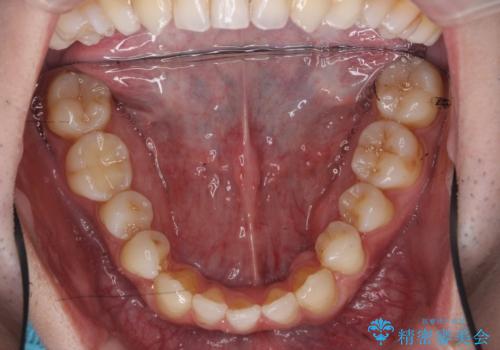

前歯の矮小歯 奥歯の反対咬合 をインビザラインで

- 上下の前歯が気になり来院。

左上2が矮小歯で小さく、また、左の奥歯が反対咬合になっていました。

左上2番はセラミッククラウンで反対側と同じ大きさにしました。

今回は下の前歯を1本抜くことで、下の奥歯をしっかり内側に傾けて治療を行いました。